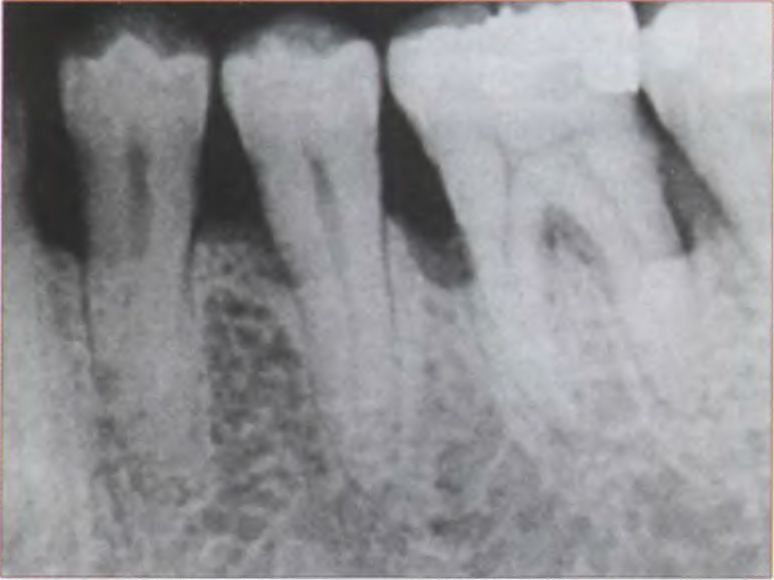

Интерпроксимальные пространства между зубами — это пространства треугольной формы, обычно заполненные тканями десны (десневым сосочком). Основанием треугольника является альвеолярный отросток, стороны треугольника - аппроксимальные поверхности контактирующих зубов, вершина треугольника находится в области контакта. Форма аппроксимального пространства варьирует в зависимости от формы зубов, находящихся в контакте, и связана с расположением контактных областей (рис. 7). В норме расстояние между эмалью и альвеолярной костью равно 1 — 1,5 мм. Таким образом, расстояние от цементо-эмалевого соединения до альвеолярного гребня кости составляет от 1 до 1,5 мм при нормальной окклюзии и здоровом пародонте.

Исследования показали, что создание правильной конфигурации аппроксимальных граней с определенным расстоянием (5 мм) от контактного пункта до костного края челюсти способствует восстановлению десневого сосочка. Край кости можно определить под анестезией с помощью инъекционной иглы. При соблюдении расстояния 5 мм и правильной технологии создания контактного пункта вероятность восстановления межзубного сосочка высока.